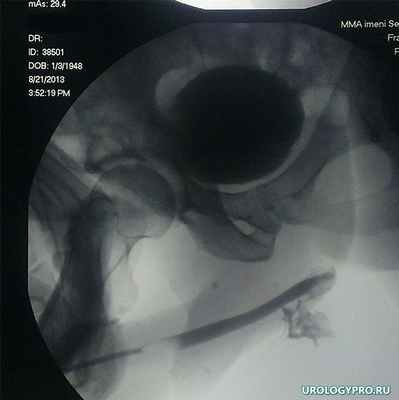

При рентгеновских методах исследований установлен разрыв луковичного отдела уретры (рис 2). 18.08.2013 выполнена ревизия правой половины мошонки, удаление гематомы. В ходе операции гематома с оболочками была мобилизована, вскрыта, эвакуировано 300 мл сгустков крови. Выявлена имбибиция начала луковичного отдела губчатого тела уретры, признаков продолжающегося кровотечения не установлено.

Рис 2. Антеградная цистограмма и ретроградная уретерограмма: установлено – герметичность мочевого пузыря не нарушена. Разрыв луковичного отдела уретры, затек контрастного вещества в парауретрные ткани.